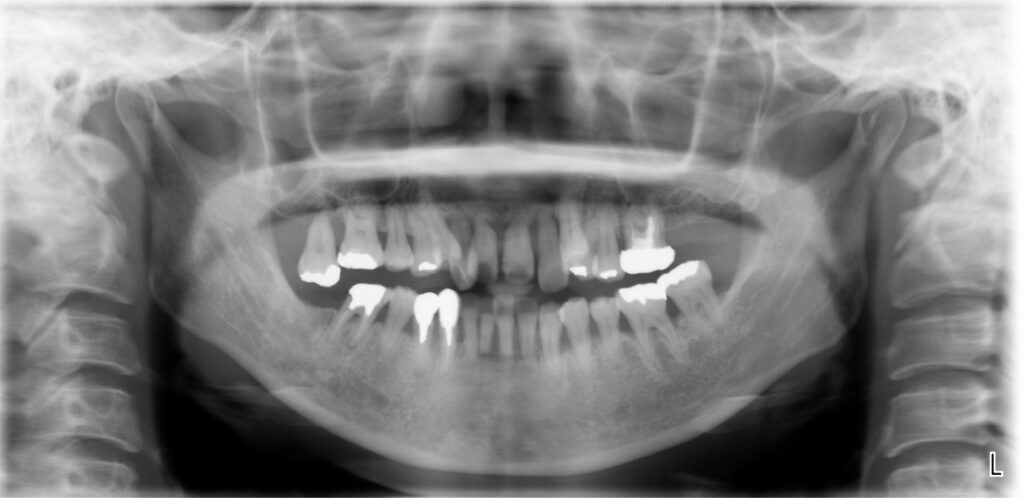

歯周再生療法 精密根管治療 歯周矯正治療 ジルコニアセラミック治療